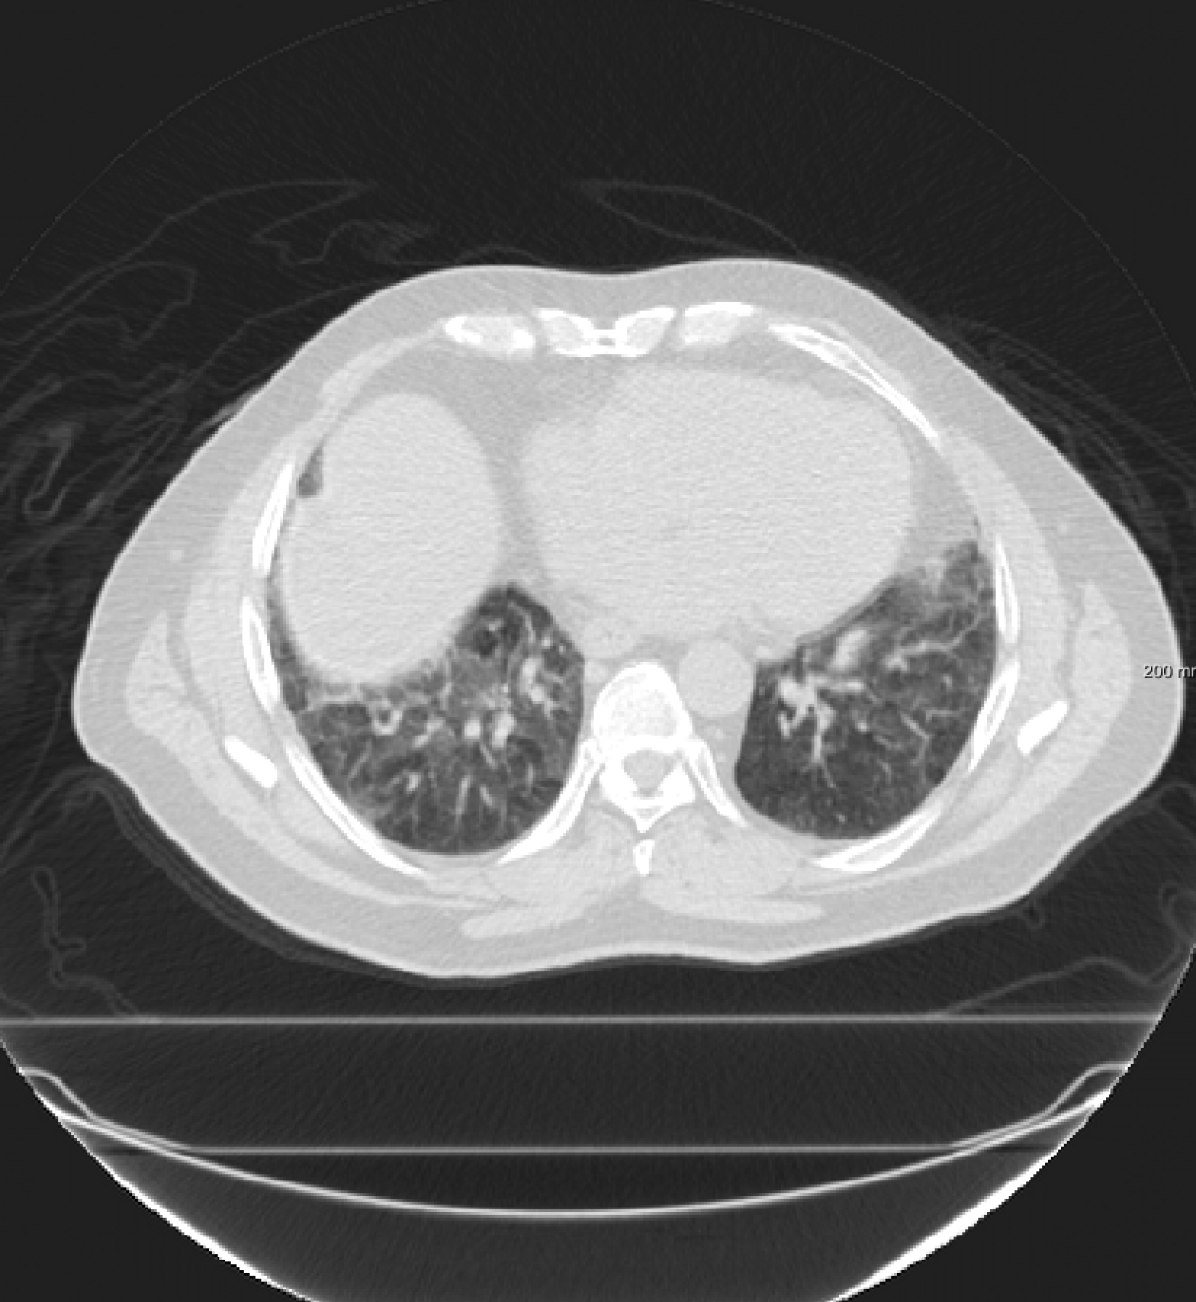

Three chest CT scan datasets are used in this study: The SPREAD (Stolk et al., 2007), the DIR-Lab-4DCT (Castillo et al., 2009) and the DIR-Lab-COPDgene dataset (Castillo et al., 2013).

In the SPREAD database, 21 pairs of 3D chest CT images are available with a baseline and a follow-up image in each pair. The follow-up images are taken after 30 months. Both images are acquired in the inhale phase. Patients in this study are aged between 49 and 78 years old. The size of the images is approximately with a mean voxel size of mm. About 100 well-distributed corresponding landmarks were previously selected (Staring et al., 2014) semi-automatically on distinctive locations (Murphy et al., 2011). Two cases (12 and 19) are excluded because of the high uncertainty in the landmarks annotation (Staring et al., 2014).

In the DIR-Lab-COPDgene database, ten cases with severe breathing disorders are available in inhale and exhale phases. The average image size and the average voxel size are and mm, respectively. In each pair, 300 landmarks are annotated.

In the DIR-Lab-4DCT database ten cases are available. We use two phases of the available data: maximum inhalation and maximum exhalation. The size of the images is about with an average voxel size of mm.

Since the convolutional neural networks process the images in a voxel-based manner, all images are resampled to an isotropic voxel size of mm.